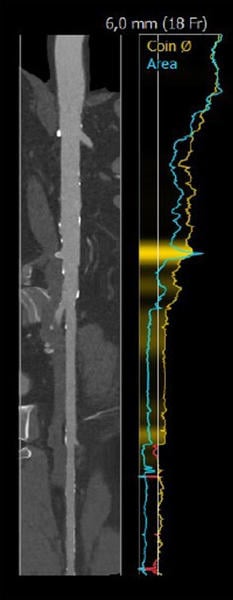

Fallplanung: CT

Anulus: 29,6 cm

LVOT: 32,2 cm

Mäßige Ca2+, Trikuspid

Sinus Vasalvae

LCA: 15,9 mm

RCA: 22,2 mm